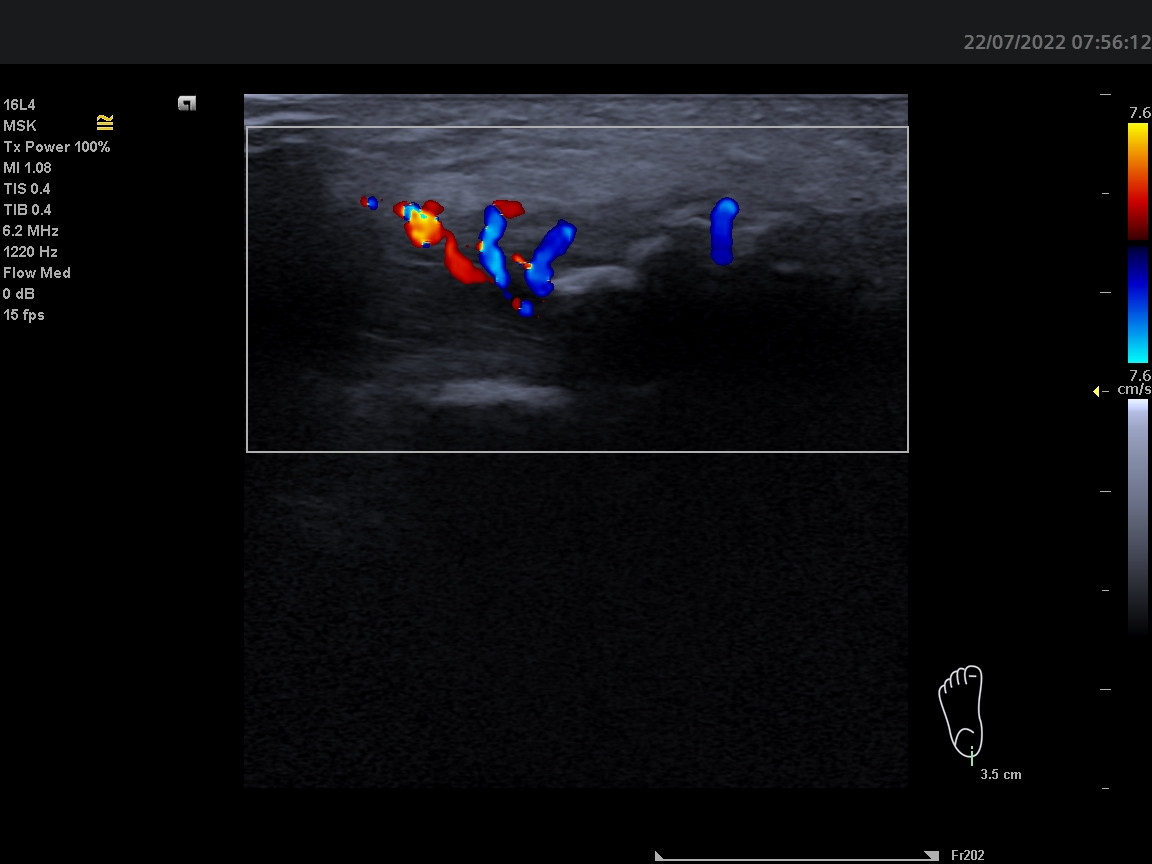

Dobrý den, ortopedem byla odeslána pacientka k revmatologickému vyšetření. 58 let, OA: HT, Psoriasis vulgartis, Asthma, HT, Barretův jícen - disp gastroenterologie. Pacientka si delší dobu stěžuje na úporné bolesti v oblasti úponu levé achillovy šlachy, dle Rtg 01/2022 dorzální i plantární patní ostruha - léčena ozařováním bez efektu. Sonograficky potvrzuji masivní patní ostruhu s mohutnými splývajícímí dopplerovskými signály v okolí i dále proximálně. Otázka: lze při této konstelaci výsledků odlišit primární psoriatickou entezitidu se vznikem masivního entezofytu od primární idiopatické patní ostruhy se sekundárním zánětem? Děkuji.

Z prosté zkušenosti mi na těchto snímcích pro jasnou entezitidu chybí hypoechogenita a zduření šlachy v oblasti enteze (zánětlivý projev) a PD signály pod 2mm od úponové kortikalis. Na snímcích chybí měřítko vzdálenosti, toto se tedy pouze domnívám. PD signály jsou ponejvíce okolo entezofytu a v proximálnějších částech šlachy. Tento nález bych hodnotila nejspíše jako tendinitidu Achillovy šlachy a masivní entezofyt, připomínajícím až Haglundovu exostózu.